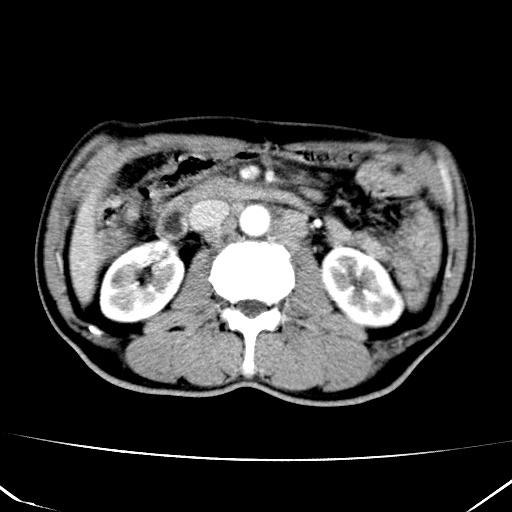

标题: CT17975:请求会诊。男、57岁。上腹部胀痛2天。临床诊断:糜 [打印本页]

标题: CT17975:请求会诊。男、57岁。上腹部胀痛2天。临床诊断:糜

肝脏多发类圆形低密度影,考虑肝脏转移瘤,肝胃韧带一淋巴结肿大,原发?胃癌?

考虑胃癌并肝脏及腹膜后淋巴结转移;不排除淋巴瘤。

肝内转移瘤,腹腔及腹膜后淋巴结转移。